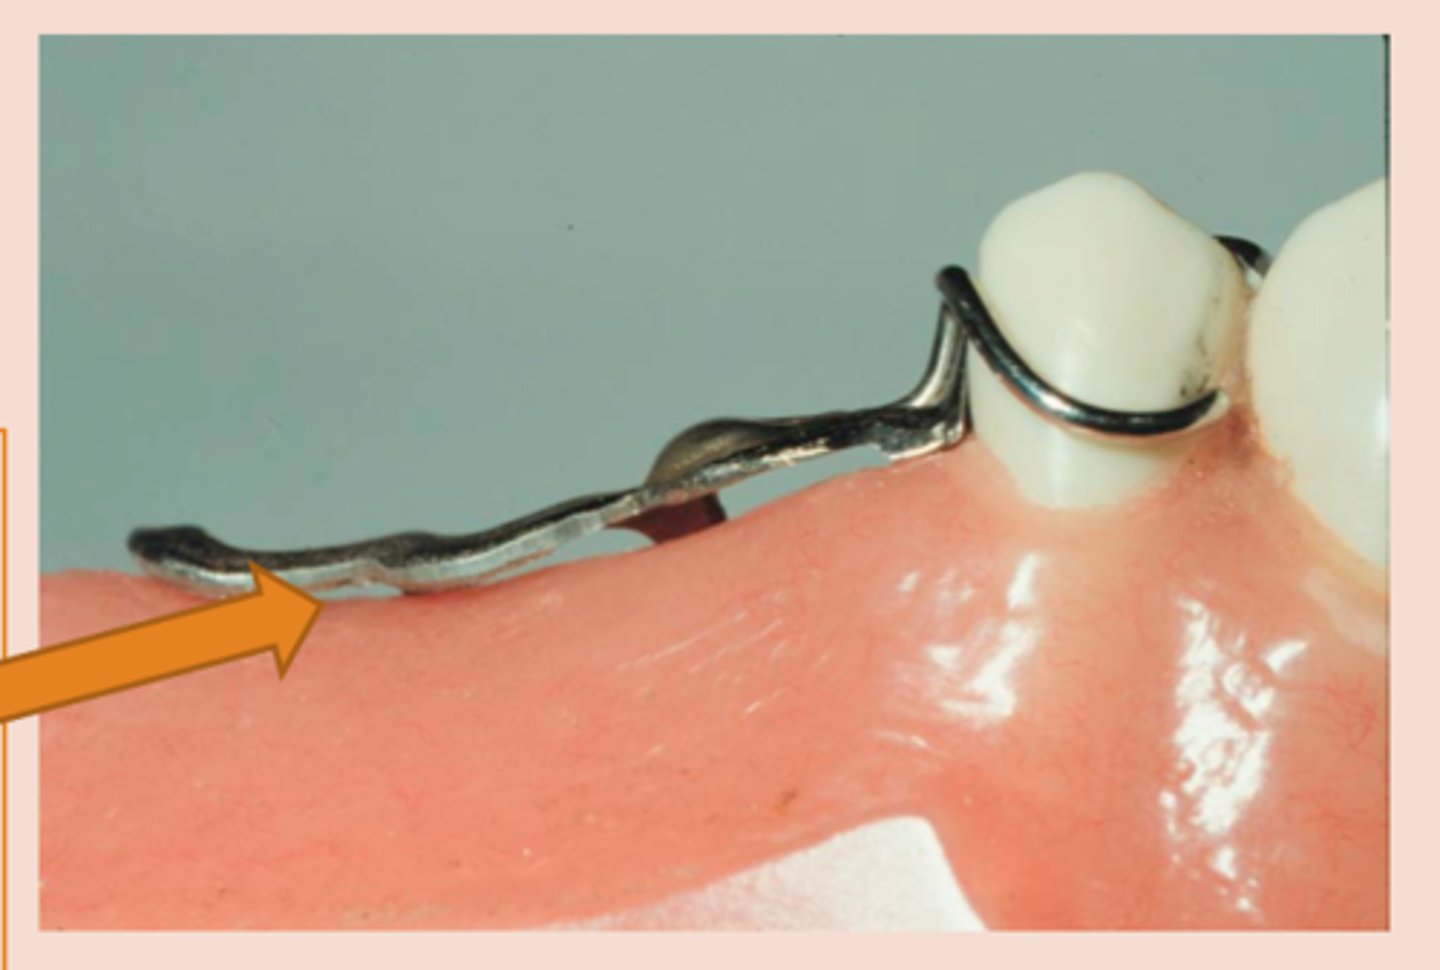

Infrabulge (Bar) Clasps

clasp

• Retentive tip in gingival 1/3 of tooth

• More esthetic

• Less contact (Hygiene)

• Cast infrabulge clasps: Stress releasing design compensates for the difference in movement between teeth and mucosa – good for adjacent to distal extension areas, if an abutment is periodontally involved, if extensive edentulous space is present

---RPI clasp assembly (MESIAL rest, proximal plate, I bar)

---Other options: T bar, half T bar, etc

MESIAL rest, proximal plate, I bar

RPI stands for

insufficient vestibular depth, large soft tissue undercuts (a)

I Bar contraindications